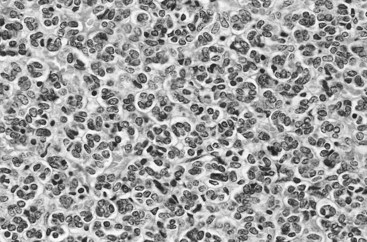

Among these, noteworthy is reninoma, which is a benign tumor of the renal juxtaglomerular cell apparatus (Wong et al, 2008). With fewer than 100 cases reported in the literature, females in the third and fourth decade are most commonly affected (Martin et al, 2001; Rubenstein et al, 2002; Wong et al, 2008). Clinical presentation is dominated by hypersecretion of renin and includes hypertension and hypokalemia and associated symptoms such as polydipsia, polyuria, myalgia, and headaches (Schonfeld et al, 1991; Rubenstein et al, 2002). The radiologic appearance is that of a small (<3 cm) solid hypovascular renal mass; and surgical excision, preferably sparing the remaining renal parenchyma, results in rapid decline of plasma rennin levels, normalization of blood pressure, and resolution of the associated symptoms (Dunnick et al, 1983; Schonfeld et al, 1991; Tanabe et al, 2001). Histologic examination reveals sheets of polygonal to spindle-shaped cells with indistinct cell borders, abundant eosinophilic cytoplasm, and minimal atypia (Martin et al, 2001). Strong immunostaining for factor VIII and factor VIII–related antigens is characteristic and confirms derivation from endothelial cell lineage (Sanfilippo et al, 1982). Although a benign clinical course is expected, one case of malignant reninoma has been documented in the literature (Duan et al, 2004).